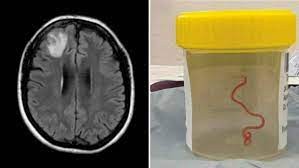

Mujer tenía una lombriz en su cerebro

Los médicos que realizaban una biopsia pensaban encontrar un cáncer o un absceso, pero hallaron en la cabeza una larva que todavía se movía.